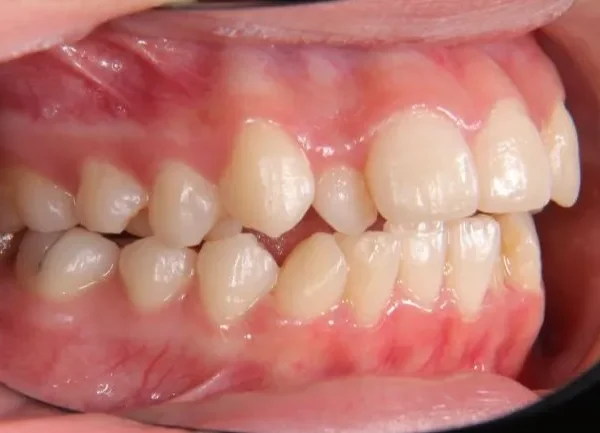

初診時年齢 高校生 (女性) 主訴 歯並びがガタガタ・口元の突出感

診断名 叢生・開咬・上下顎前突 装置名

特徴 ゆがんで生えている

状態 ガタガタ・でこぼこに生えている(叢生)

受け口(下顎前突/反対咬合)

前歯で噛めない(開咬/オープンバイト)

上下前歯、口元が出ている、口ゴボ(上下顎前突)

ガタガタの歯並びにお悩みの患者様でした。

口唇の突出感の他、下顎面高が長い印象も認められました。